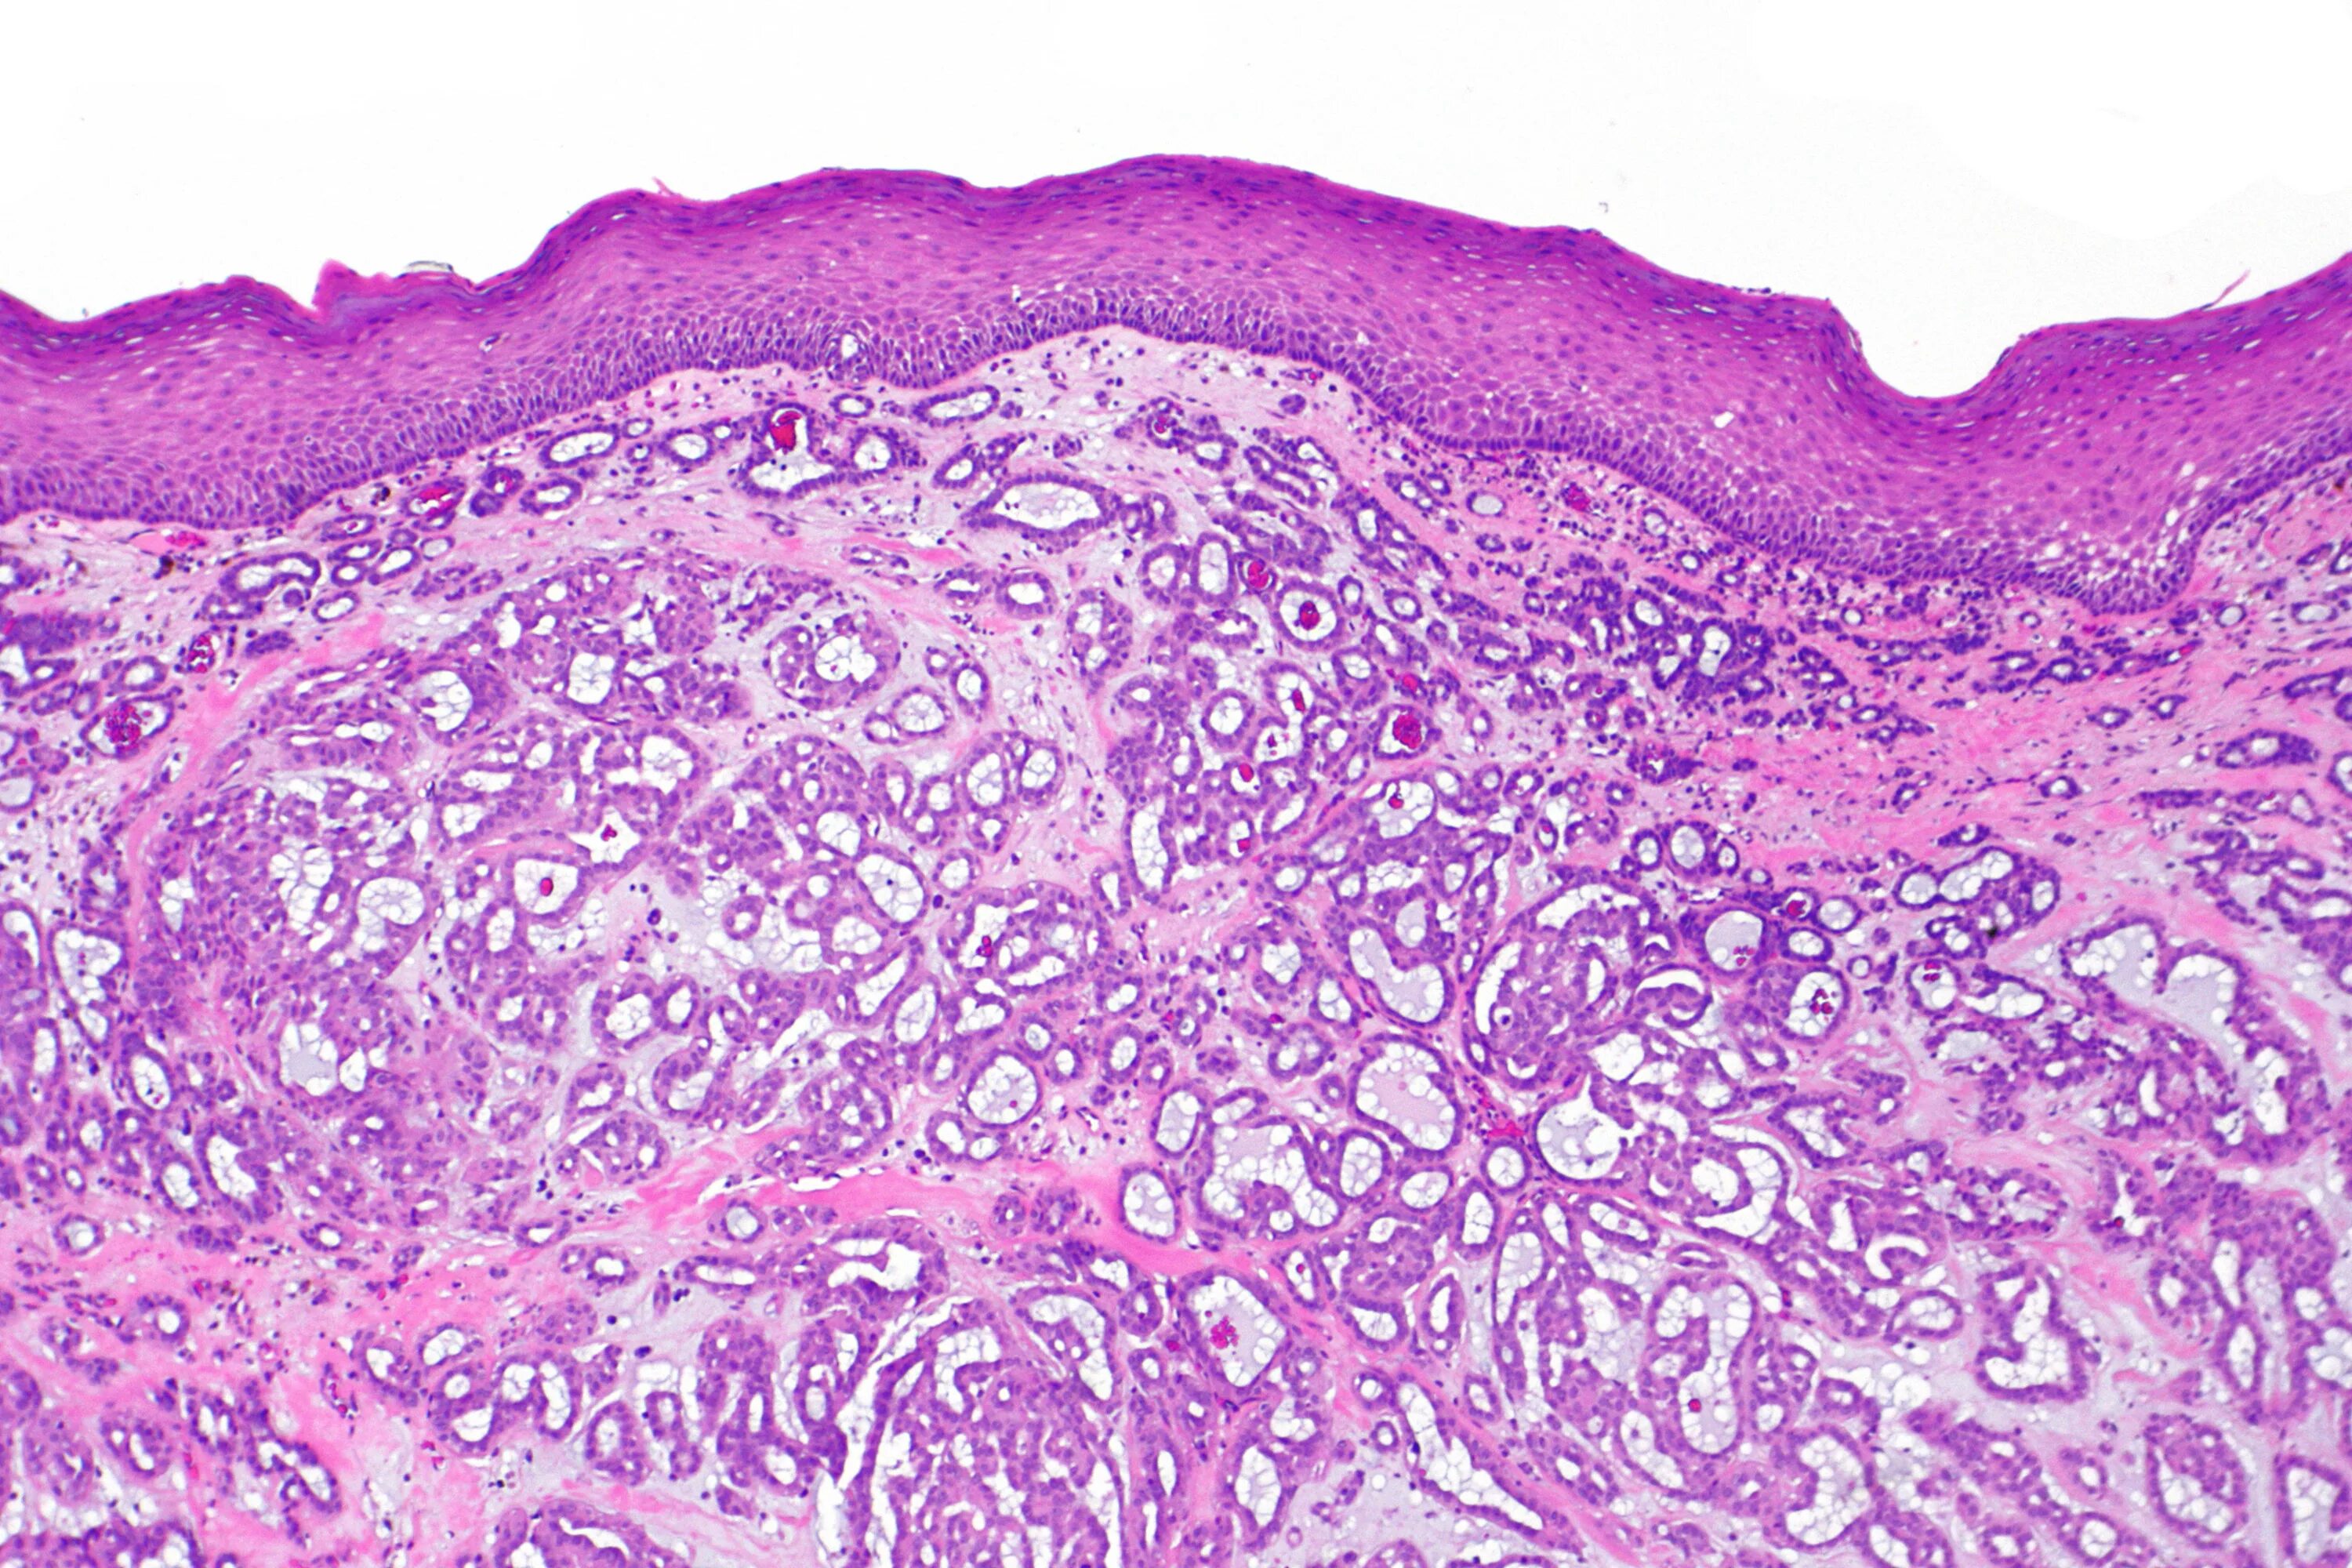

Гистологически аденокарцинома